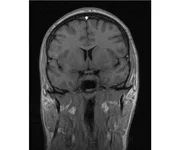

делал в обласной на siemense.В заключении выданом мне через 15мин.после мрт (легкая дегидрация)

Меня смутил факт выдачи заключения через 10мин(наверно они у них зарание напечатаные)я не медик.достаточно мимолётного взгляда на снимки?А вы видете на них гидроцефалию? Я лиш спросил куда идти с результатами томографии?и не хотел никого роздражать.

Я попросил взглянуть на снимки и сказать видна.ли на них гидроцефалия?или куда обратится за консультацией по этому вопросу?В мрт снимках наверно розбирается любой нервопатолог(я так предположил)

Я уже говорил, что независимо от того, есть на МРТ гидроцефалия или нет, лечиться тебе нужно только в том случае, если есть какие-либо проявления болезни, иначе на все эти анализы можешь забить... Но давай все-таки разберемся с томограммой.

Итак, с самого начала томограмма обозначала срез какого-либо органа на определенной глубине, позволяла заглянуть вовнутрь. При компьютерной томографии аппарат делает десятки срезов головного мозга в разных направлениях и из этого множества срезов он моделирует полноценное объемное изображение мозга в натуральную величину. Обрати внимание, компьютер работает не с этими миниатюрными изображениями, а с трехмерной моделью в масштабе 1:1. Эту модель вдоль и поперек анализирует суперсовременный компьютер, выполняющий миллионы операций в секунду. Только ***** может пытаться перепроверить компьютер, ведь человеку не хватит всей жизни чтобы проанализировать то, что компьютер с тобой сделал за 10 минут. Я хочу, чтобы ты это понял!

Ты разместл здесь несколько миниатюр и хочешь, чтобы врач по ним создал полноценное объемное изображение в натуральную величину, а потом осмотрел его со всех сторон и дал заключение? Но ведь это невозможно. Это просто насмешка над врачом, это издевательство над здравым смыслом. Принеси Букеру уменьшенный в 50 раз снимок зуба и спроси у него, в каком состоянии там корневые каналы. Или давай я дам тебе скрин со спутниковой карты города и попрошу тебя описать, какого цвета и какой модели запечатленная со спутника машина, какой у нее гос.номер, сколько в ней пассажиров, сколько из них мужчин и сколько женщин...

Надеюсь, ты понимаешь, что это невозможно. И воссоздать по приведенным тобой аватарам полную картину мозга тоже невозможно. Пойми, если уж называть вещи своими именами, то ты запостил полнейшую ***ню! Ты не хотел никого обидеть, ты ведь сам не ведал, что творил. Ты продемонстрировал полнейшую медицинскую безграмотность и полное невежество, но претензий к тебе нет. Ты ведь не один такой. Ты пожелал того, что сделать невозможно, и тут же у тебя нашлась сочувствующая, некая П., которую, по большому счету, надо бы послать в П., коль уж она считает, что врач должен тут сделать немедленно и бесплатно то, что делает немецкий компьютерный томограф ценой в миллионы долларов.